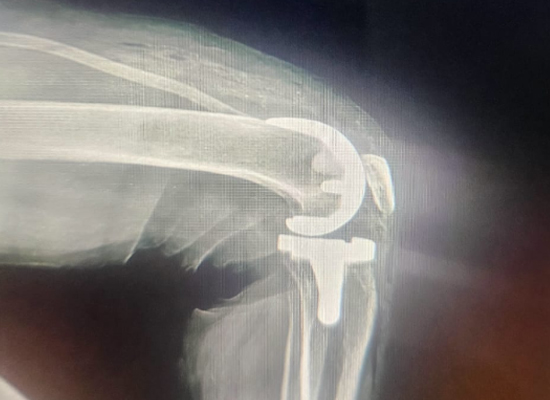

Postoperative Imaging

Knee Surface Replacement for Right Knee Deformity And Dysfunction-czmeditech5

Postoperative X-ray - Lateral View